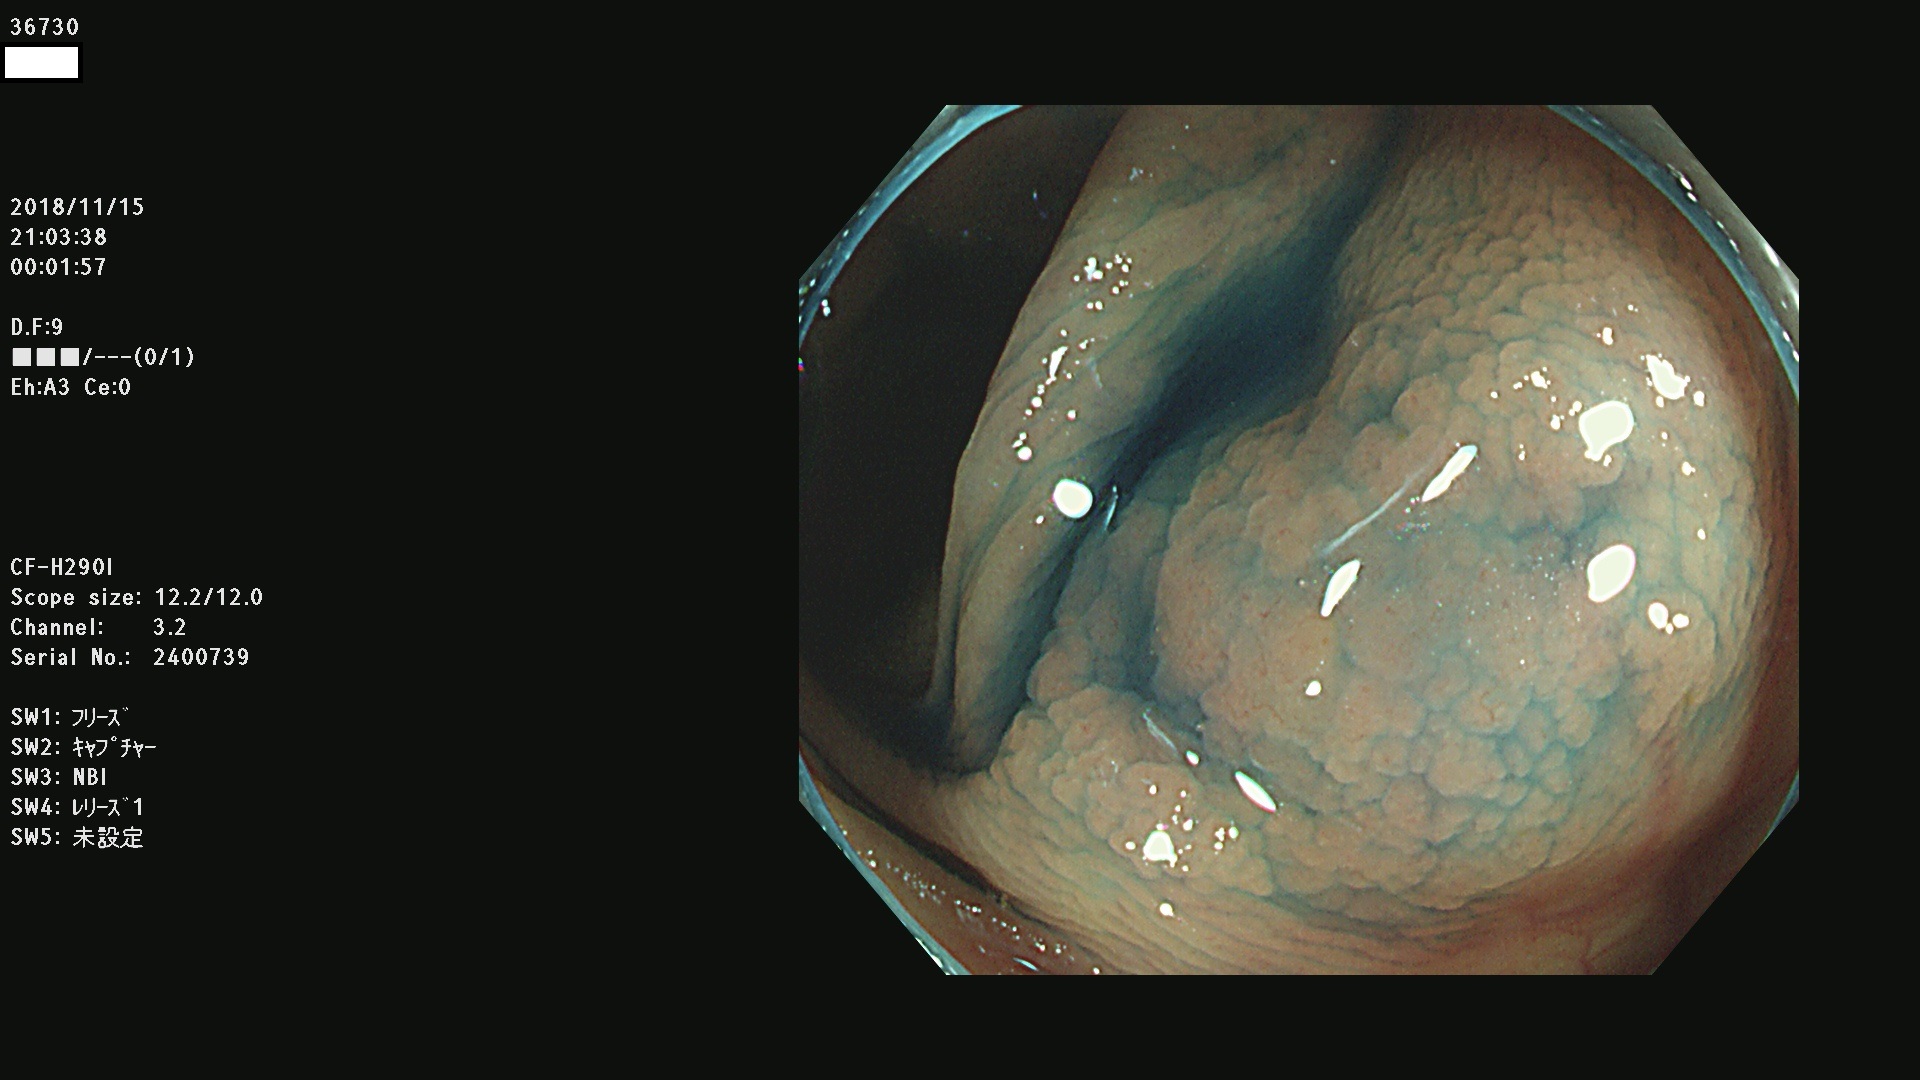

36700 36701 36702 36704 36705 36707 36708 36710 36712(SSAPのみ) 36714 36715 36716 36717 36718 36721 36723 36724 36730 36731 36732 36734 36735 36736 36738 36739 36742 36744 36745 36746 36749 36752(SSAPのみ) 36754 36756 36758 36759 36760 36731 36732 36734 36737 36738 36739 36771(SSAPのみ) 36772 36773 36774 36775 36776 36777 36780 36781 36783 36785 36786 36788 36790 36792 36794 36797 36798

発見困難で危険性の高い平坦型病変(上記100名より抽出)